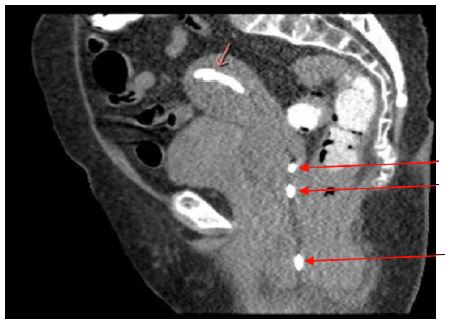

The patient represented on POD 18 again with fever and worsening perineal pain. She was febrile, white blood cell count was elevated, and CT showed a similar fluid collection in the uterus and re-accumulation of the perineal abscess (Figure 2). She was admitted for antibiotic administration and interventional radiology was consulted for drainage of the two areas of abscesses. On POD 19, a drain was placed vaginally into the uterus as well as a second drain into the perineal collection (Figures 3 & 4). The cultures ultimately revealed multidrug resistant Escherichia coli and Enterococcus raffinosus. She was subsequently treated with Meropenum. The patient improved and was discharged home on POD 27 without any further treatment necessary.

Figure 2: POD 18 – Reaccumulation of the abscess that was multilocular (outlined by a red oval) extending from the level of the posterior vagina to the left of midline and extending superiorly for about 10 cm to the level of the lower uterine segment. Fluid within the endometrial cavity measuring 4.6 x 3.3 cm (thick red arrow). Bladder shown with a thin black arrow.